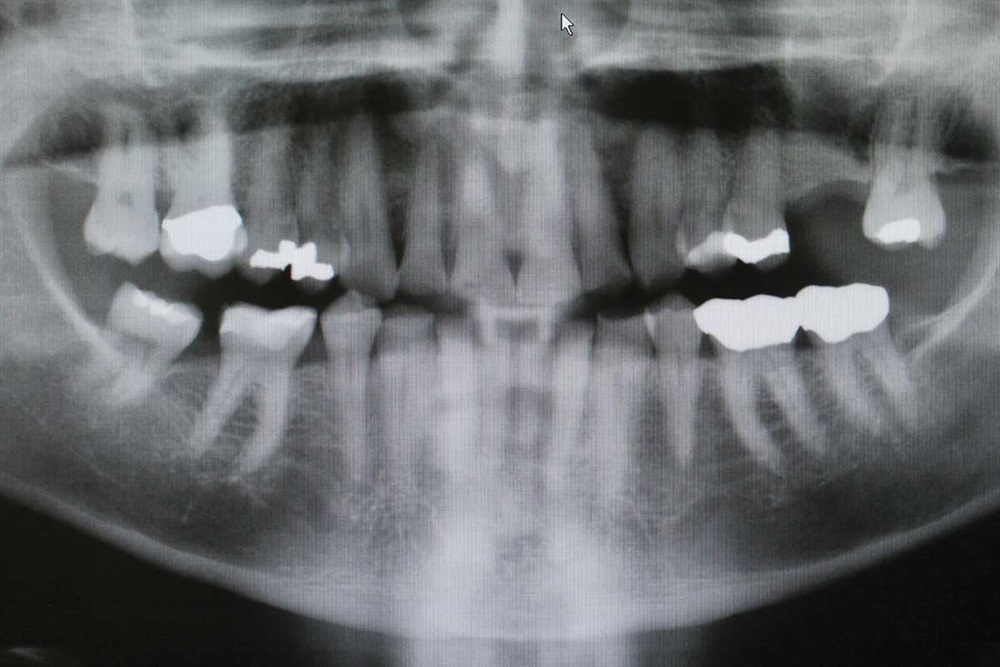

Fig. 4: Panorex, part 1. Gold crowns on the lower left, PFM on right maxillary molar.

Fig. 5: Close-up of Panorex.